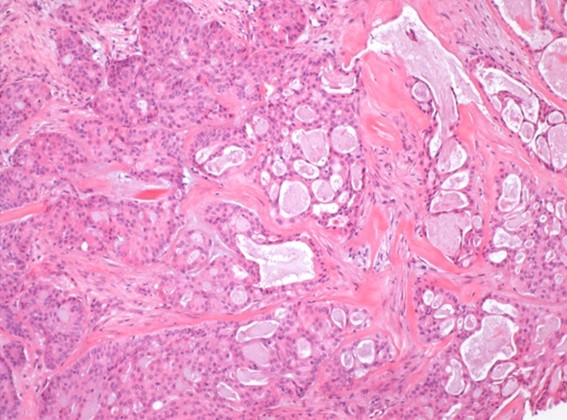

Histopathological evaluation showed a tumor with cribriform and microacinar architecture embedded in a sclerotic stroma, with three different cells populations: mucinous, squamoid and intermediate cells (Fig. 5). No signs of true keratinization or high-grade features were found.

Figure 5: Microscopic sections showed a tumor with cribriform/microacinar architecture in a background of stromal sclerosis. The majority of cells showed round nuclei and abundant eosinophilic cytoplasm. Peripherally, cells with small uniform nuclei and dense cytoplasm were seen. Presence of extracellular and intracytoplasmic mucin was observed. (HE, x100).

Immunohistochemically, CK7 presented strong positivity in mucinous cells while p63 a CK14 stained both intermediate and squamoid cells. CD117, HER2 and hormonal receptors were negative. A MAML2 gene rearrangement was detected by FISH in 76% of the analyzed cells.

Considering all the aforementioned features, the diagnosis of grade 2 mucoepidermoid carcinoma of the breast was made.